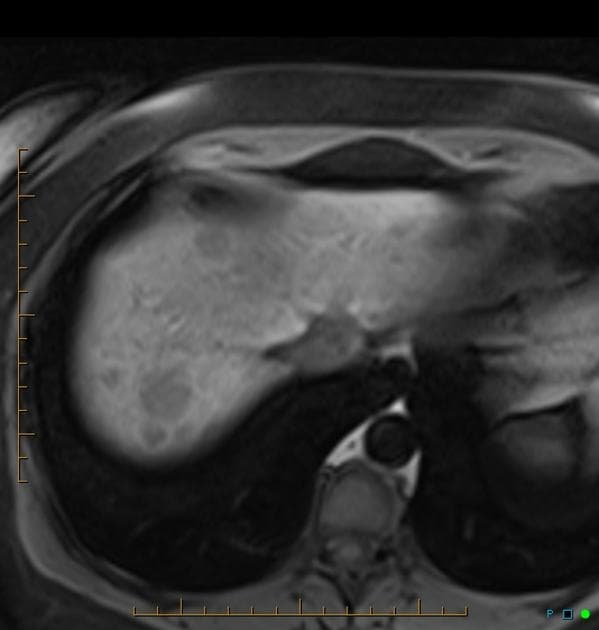

Axial C+ portal venous phase

- Khối tổn thương tăng tưới máu thì động mạch (arterially hypervascular) kích thước 37×32 mm, có sẹo trung tâm không ngấm thuốc, nằm ở phân đoạn V của gan; khối này trở nên đồng tỷ trọng (isodense) so với nhu mô gan xung quanh ở thì tĩnh mạch cửa (portal venous) và thì chậm (delayed).

- Các đặc điểm trên chụp CT phù hợp nhất với chẩn đoán tăng sản tuyến focale (focal nodular hyperplasia), đây là tổn thương gan lành tính phổ biến thứ hai (phổ biến nhất là u mạch gan - hepatic hemangioma). Trên hình ảnh sau tiêm thuốc cản quang, tăng sản tuyến focale (FNH) thể hiện ngấm thuốc đồng nhất và đậm ở thì động mạch, trừ phần sẹo trung tâm vẫn giảm tỷ trọng (hypoattenuating).

- "Đặc điểm hình ảnh điển hình gồm tăng tưới máu thì động mạch, ngấm thuốc đồng đều và sẹo trung tâm không ngấm thuốc."

- "FNH thường trở nên đồng tỷ trọng so với nhu mô gan ở thì tĩnh mạch cửa và thì chậm, giúp phân biệt với u tuyến gan."

Tăng sản tuyến focale (FNH) là tổn thương gan lành tính, được cho là do phản ứng tăng sản tại chỗ trước một bất thường mạch máu khu trú, thường liên quan đến dị dạng động-tĩnh mạch. Bệnh phổ biến ở phụ nữ trẻ đến trung niên và thường không có triệu chứng, được phát hiện tình cờ khi chụp hình. Đặc điểm điển hình trên CT hoặc MRI là khối tổn thương ranh giới rõ, tăng tưới máu mạnh ở thì động mạch, có vệt sẹo trung tâm hình ngôi sao không ngấm thuốc. Ở thì tĩnh mạch cửa và thì muộn, tổn thương trở nên đồng tỷ trọng hoặc đồng tín hiệu so với nhu mô gan xung quanh do giữ thuốc dần dần. Sự hiện diện của sẹo trung tâm và không có hiện tượng tẩy thuốc giúp phân biệt FNH với u tuyến gan và các tổn thương ác tính. Sinh thiết hiếm khi cần thiết nếu hình ảnh điển hình.